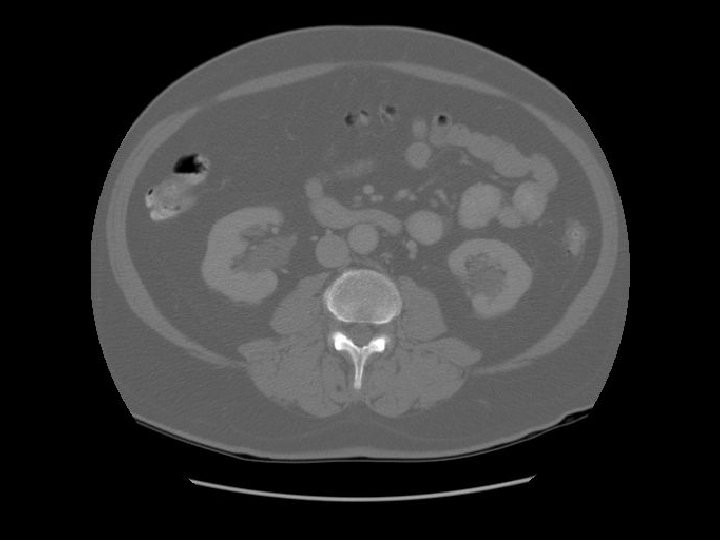

Kidney Right Kidney

Descending colon Right

Renal pelvis

Ascending colon Right colon with fecal material.